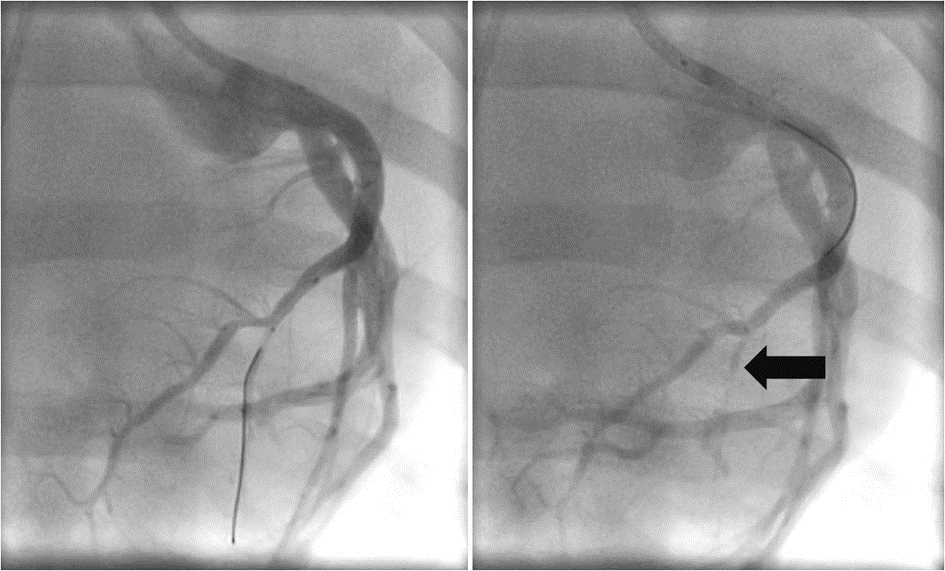

Transcoronary ablation. The mean ablation duration was 10.3 seconds at 20 W with an initial impedance of 176 ± 31 Ώ. After the transcoronary RF ablation, the intended occlusion of the coronary vessel (thrombolysis in myocardial infarction [TIMI]-0 or TIMI-1 flow) could be verified by angiography in 82% of the septal branches attempted and 79% of the epicardial branches (Figures 6 and 7). No unintended occlusions of the main vessel occurred in any case.

Vessel occlusion by RF delivery

Unlike the studies mentioned above, our group intended to occlude the coronary side branch by RF delivery. A total occlusion or a no-reflow could only be achieved in about 80% of the vessels attempted within 1 or 2 RF deliveries at a mean cumulative duration of 10.3 seconds. It is possible that a higher success rate could be achieved by cooling the guidewire by saline infusion via a microcatheter, as described by Xuan et al,14 allowing longer ablation durations. However, even in the standard TASH procedure, the occlusion rate of the septal branches treated with ethanol injection is not 100%. Furthermore, even if there is still a TIMI-1 flow, the acute myocardial necrosis induced by the RF delivery surrounding the vessel should impair a normal transfer of oxygen and substrates to the surrounding myocardium. The acute ablation lesions could be demonstrated in our series in the fresh explanted hearts during the macroscopic and histological evaluation after fixation.